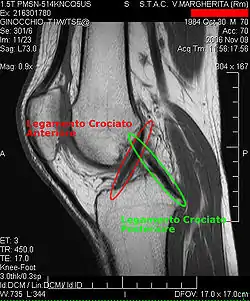

Procédés d'imagerie

Le diagnostic peut être confirmé par imagerie (IRM). Mais il faut noter que l'interprétation de l'IRM seule pour le diagnostic de rupture de LC conduit à 20 % de faux diagnostics. Cela dépend des images de coupe et de la position appropriée du genou pendant l'IRM. Le radiologue doit connaître avec précision les circonstances qui ont conduit à la blessure, et avoir aussi une bonne expérience de l'étude d'une articulation blessée, pour éviter les faux diagnostics. Pour comparer avec l'IRM, le taux d'erreur du test de Lachman, bien plus simple à accomplir, n'est que de 10 %[104],[105],[106],[107]. L'IRM est donc généralement moins sensible et moins spécifique que l'examen clinique par un orthopédiste qualifié[108]. Le résultat de l'IRM n'a que relativement rarement une influence sur la formulation finale du diagnostic[109] et ne devrait pas servir de remplacement pour une anamnèse soigneuse et la palpation[15]. Plusieurs études arrivent à la conclusion que l'IRM n'a de sens que pour des blessures complexes difficiles à expliquer, et là, pour éviter de poser un diagnostic négatif[110],[111],[112].